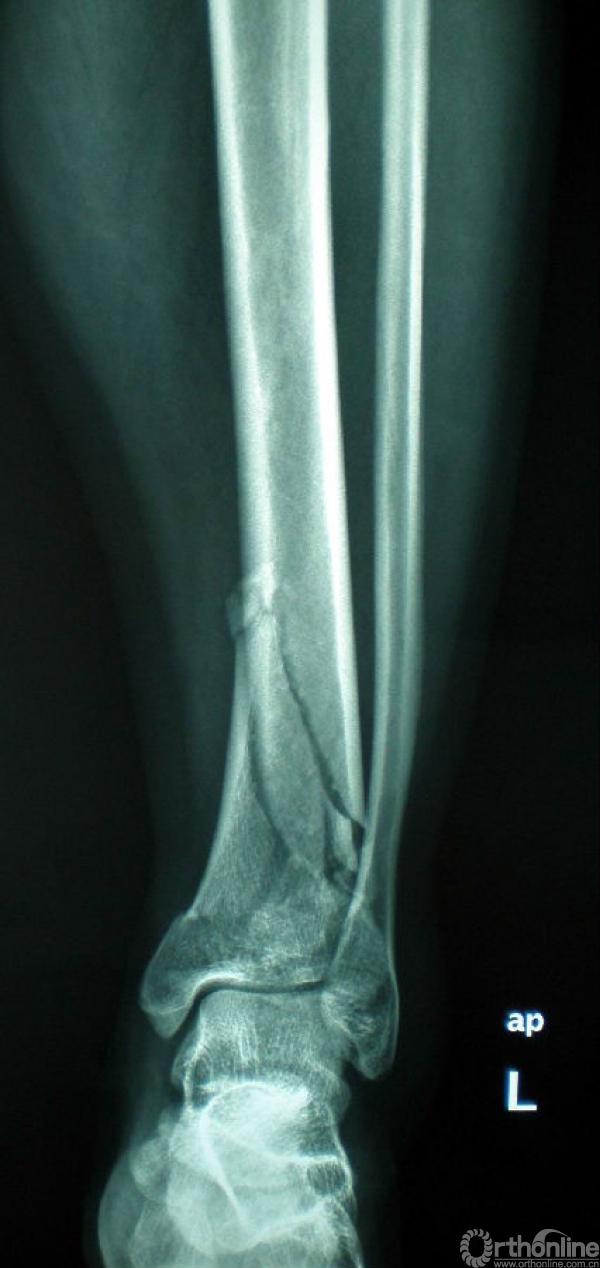

图4 男,41岁,左侧双柱pilon骨折。

4a.术前正位、侧位X线示胫骨远端粉碎性骨折,属于外侧柱的腓骨完整;

4b.CT水平面扫面及表面重建示内侧柱及中柱有明显的骨折;

4c.手术入路及1/3半管型钢板分柱固定情况;

4d.术后X线正侧位片示双柱pilon骨折对位、对线良好。